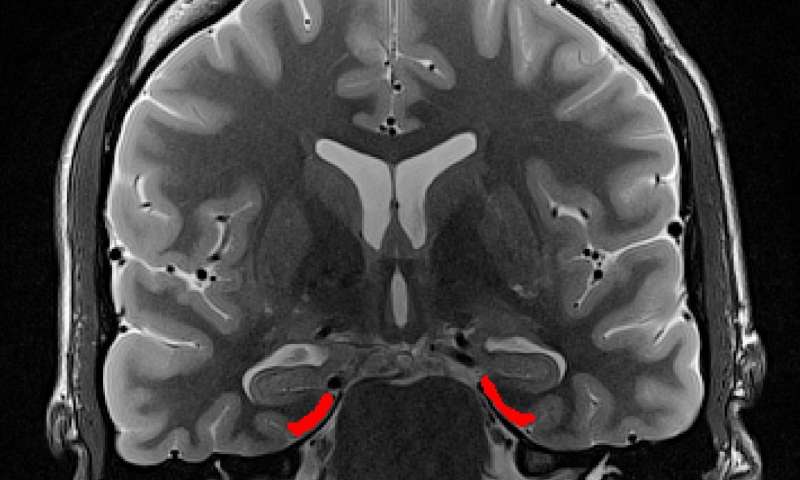

“Quando ti muovi in un ambiente non familiare, è perfettamente normale perdersi, ma questo tende ad accadere più spesso alle persone anziane. “Finora, sappiamo molto poco sui meccanismi neuronali sottostanti questi problemi di navigazione “, afferma Matthias Stangl , ricercatore presso il Magdeburg di DZNE e primo autore dell’attuale pubblicazione. “Avevamo ipotizzato che le cosiddette cellule della griglia potessero essere implicate in queste difficoltà: una parte importante dell’elaborazione della navigazione viene effettuata da queste cellule che sono neuroni specializzati situati nella corteccia entorinale del cervello, quindi abbiamo intuito che i deficit nella funzione delle cellule della griglia potrebbero essere causa di problemi nella navigazione “.

“Tutto sommato, i giovani partecipanti hanno mostrato migliori capacità nella navigazione, che è in linea con gli studi precedenti, tuttavia abbiamo trovato un’associazione tra diminuzione della prestazione di navigazione e deficit nell’attività delle cellule della griglia“, afferma il Prof. Thomas Wolbers, uno scienziato senior e supervisore DZNE dello studio attuale. “Le cellule della griglia si sono attivate in modo diverso quando si confrontano adulti giovani e meno giovani, in particolare gli schemi indicano che questi circuiti cerebrali sono compromessi in età avanzata. causando problemi con la navigazione spaziale”.

Wolbers aggiunge: “Le cellule della griglia svolgono un ruolo centrale non solo nella navigazione, ma anche in altre funzioni cognitive, pertanto i nostri risultati potrebbero indicare un meccanismo chiave alla base dei deficit cognitivi in età avanzata e forniscono informazioni sui cambiamenti neurofisiologici dovuti all’invecchiamento. I risultati possono anche aiutare nella progettazione di terapie contro il declino cognitivo legato all’età “.